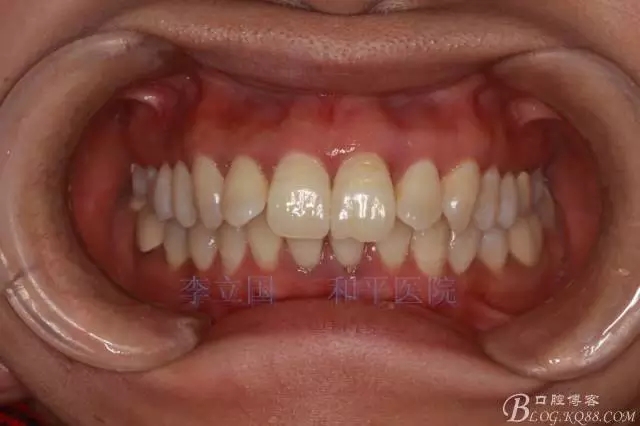

”嘴凸牙不凸”病例治療要點(diǎn)

患者主訴前突。

1.患者上前牙直立,面型前突,典型的嘴凸牙不吐,關(guān)鍵是前牙轉(zhuǎn)矩控制,建議使用高轉(zhuǎn)矩托槽。

2.磨牙關(guān)系一側(cè)完全遠(yuǎn)中,一側(cè)遠(yuǎn)中尖対尖,采用兩個(gè)上4,一個(gè)下1的拔牙模式。